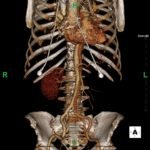

Because aortic dissection was suspected, the patient underwent urgent computed tomography (CT) angiogram of her chest, abdomen and pelvis that revealed her diagnosis.

The patient was found to have a Stanford type A dissection (see yellow arrow) with visible false lumen starting at aortic arch (see green circle). The dissection extended into the descending aorta (see blue circle) as shown by the false lumen (red highlighted area) visible on CT. The radiologist performed a reconstruction of the aorta, which showed that the left kidney was not being perfused, making the kidney not visible on the reconstruction.